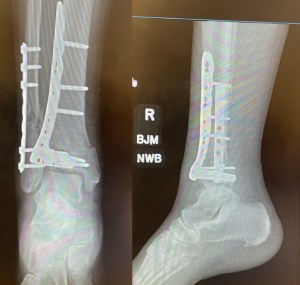

I’ve been given permission to show what her ankle is looking like so far.

At our appointment last Monday, the surgeon decided to leave the stitches for another week because the residual swelling was still putting pressure on the wounds. That swelling has come down nicely in the days since. He anticipated that the numbness Cyndie was experiencing would diminish as the nerve root-like structures that were disrupted grow back.

- Surgery for Cyndie’s broken bones is scheduled for tomorrow. We met the surgeon yesterday and like him a lot.

- Cyndie’s bone breaks just above her ankle are not clean but they are not as bad as what is commonly seen in a fall from a roof or an automobile accident.

- Cyndie had a CT scan yesterday to confirm there is no damage to the ankle joint. The joint looks good in the X-rays. The surgeon is confident it won’t be a problem to stretch the tendons and ligaments enough to straighten her foot from the odd angle it has acquired since the bones broke.

- John will be required to cover for Cyndie in walking the dog and tending to the horses for a minimum of 8 weeks. The surgeon said she will be able to do therapy exercises and flex the ankle sooner than that, but he doesn’t want her to put any weight on it until after the 8 weeks.

An x-ray confirmed both the tibia and fibula were broken just above the ankle and she will require surgical repair.